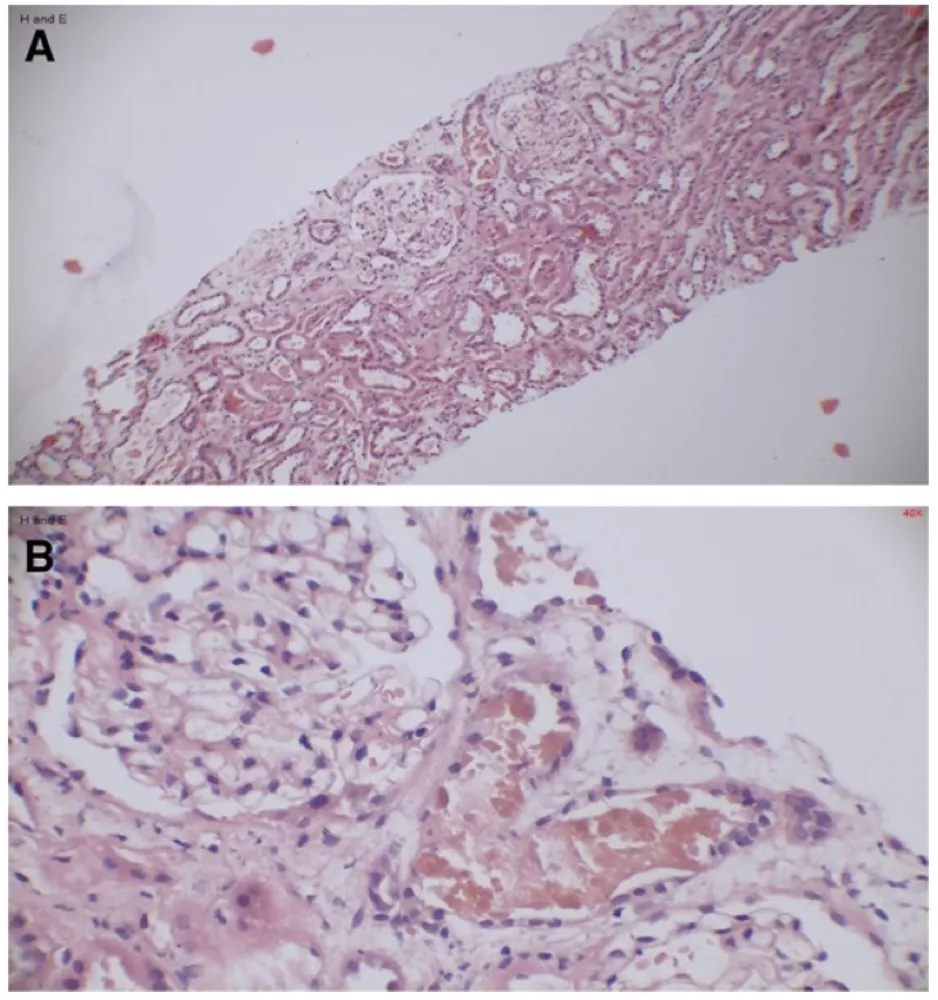

Proteinúria persistente, dor neuropática e lesões cutâneas podem parecer desconexas, mas, quando analisadas em conjunto, revelam a Doença de Fabry. Este caso ilustra como a integração entre clínica, biópsia renal, estudo enzimático e genética conduz a um diagnóstico preciso e a um manejo precoce, com impacto direto no prognóstico do paciente e de sua família.

Valkercyo Feitosa

11 meses atrás